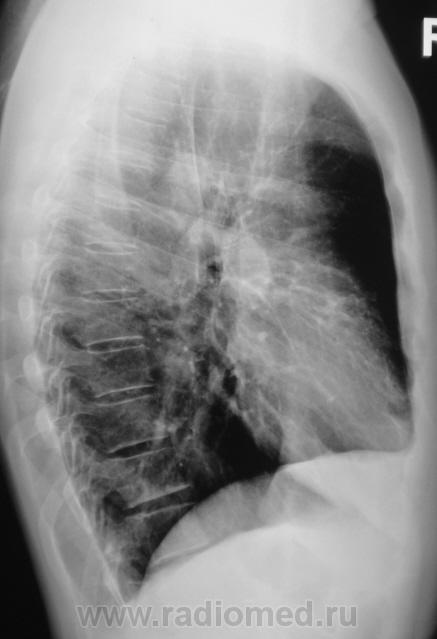

Еще контроль через 1 месяц.

Распад был изначально, но, к счастью больного, все закончилось практическим выздоровлением.

Долго что-то пневмонию лечили. А распад очень сомнительный. Больше на игру теней похож.

Да, лечение весьма затянулось.